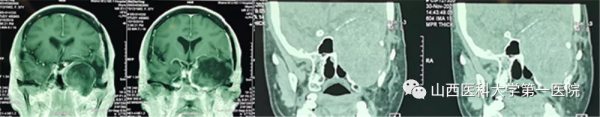

患者是一名老年女性,早在7年前診斷為顱底“膽脂瘤”,7年來已經接受了三次開顱手術治療,近期出現的頭痛、視力減退、面部麻木等症狀預示著腫瘤可能再次復發。經MRI和CT檢查後發現其腫瘤不僅復發,而且較以往體積明顯增大,最大直徑達8.5cm,最麻煩的是腫瘤所處的位置非常“尷尬”,像一顆“炸彈”深深地卡在了中顱底,約1/4部分瘤體位於顱腔,其餘3/4凸向翼顎窩、顳下窩。“巨大的腫瘤體積、複雜的解剖位置、既往多次手術史”等不利因素,為本次手術治療帶來了巨大挑戰。術前由醫務處牽頭組織由口腔頜面外科、神經外科、麻醉科、手術室等組成的多學科團隊對手術方案進行了周密部署,對術中風險進行了充分評估並制定了應急預案。

經過對“手術入路、硬腦膜修補、顱底缺損重建、頸內動脈和海綿竇等毗鄰結構保護”等系列高風險環節的反覆研究,最終定為由口腔頜面外科先行頸-頜入路、上頜骨、顴骨部分切除,充分顯露後先切除顱外3/4部分瘤體,再透過顱底骨缺損“視窗”由神經外科完成顱內部分瘤體的切除與硬腦膜的修補,最後採用股前外側肌皮瓣遊離移植修復顱底、翼顎窩、顳下窩巨大無效腔。為了使手術方案進一步可靠,口腔頜面外科團隊術前採用數字化技術對手術入路進行了虛擬驗證,並從三維立體方向對腫瘤周圍的重要結構進行全方位掌握。